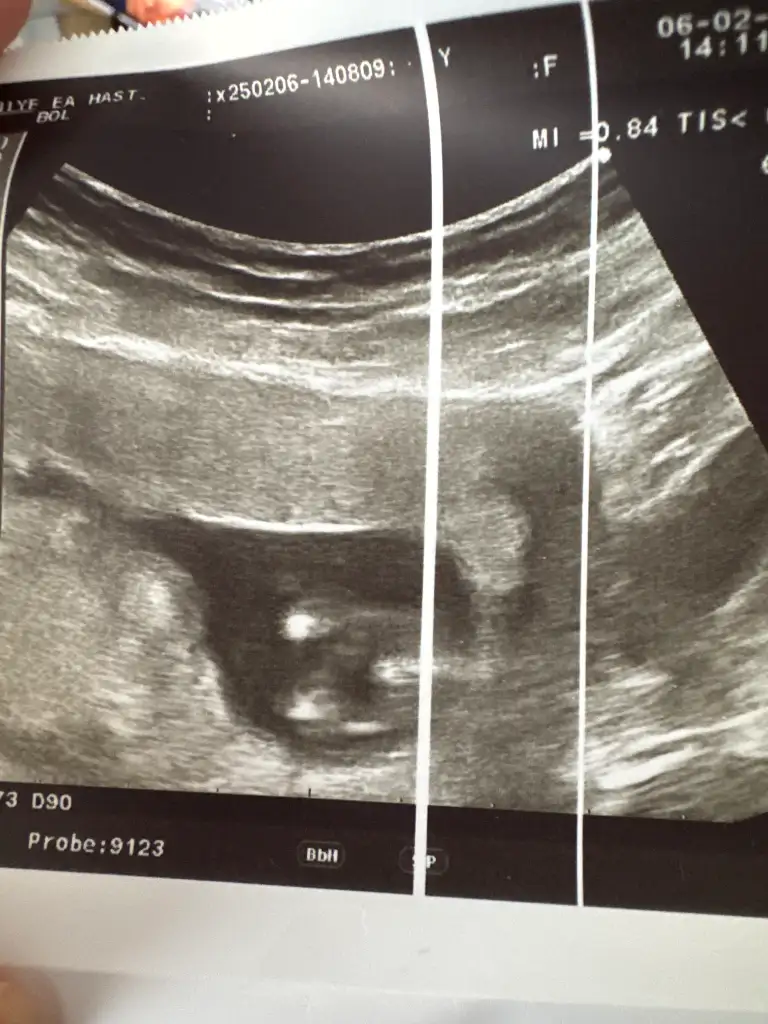

Benim 12 ve 13 haftalık görüntüye benziyor ama bana da kordon iki bacağının arasında yine de yüzde doksan erkek gibi dedi şu an 16 haftalık haftaya tekrar gidicem15+3 günlük doktor kıza benziyor dedi ama ben erkek görüyorom. Sizce?

13. Haftada da böyle göründü15+3 günlük doktor kıza benziyor dedi ama ben erkek görüyorom. Sizce?

Haber edin lütfen. 3 hafta sonra gel dedi bana. Bekleyelim bakalımBenim 12 ve 13 haftalık görüntüye benziyor ama bana da kordon iki bacağının arasında yine de yüzde doksan erkek gibi dedi şu an 16 haftalık haftaya tekrar gidicem

Foto net diğil. Amma erkek gibi hiss etdim. Sizde 16-haftamı burda?Benim 12 ve 13 haftalık görüntüye benziyor ama bana da kordon iki bacağının arasında yine de yüzde doksan erkek gibi dedi şu an 16 haftalık haftaya tekrar gidicem

Yok şu an yeni 16 hafta oldu. Resimlerdeki 12 ve 13 haftalık görüntüsüFoto net diğil. Amma erkek gibi hiss etdim. Sizde 16-haftamı burda?